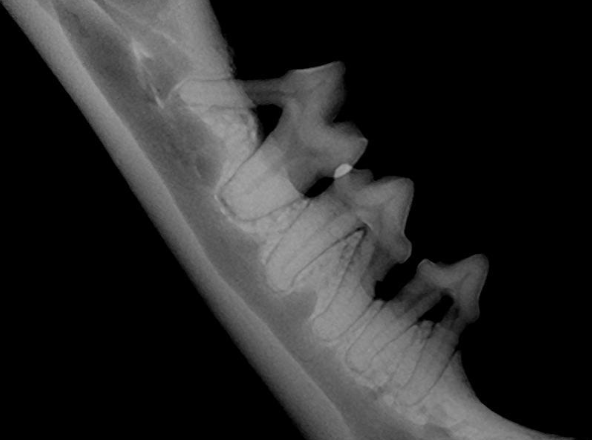

Quel est l’index parodontal de la dent 409?

PD4

Théorie :

- PD0 = parodonte sain, pas de perte osseuse

- PD1 = gingivite, pas de perte osseuse

- PD2 = parodontite < 25% perte osseuse

- PD3 = parodontite 25-50% ou furcation 2

- PD4 = parodontite > 50% ou furcation 3